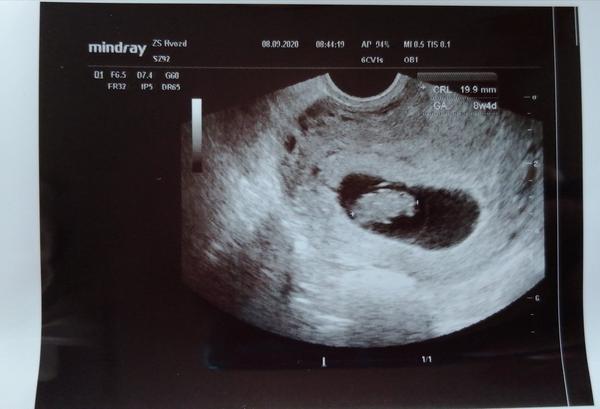

@pecenacek zlatí já mám nevolnosti už asi 3 týdny jako mazec se zachode to máme stejně a odpoledne proste po obědě potrebuju spát 🤣unavená jsem nonstop jako bych vůbec nespala 😁🤷♀️ máme ultrazvuk za sebou a super mimi je o 9 dní větší odpovídá 8+2 tak jsme stastni😍😍😍držím palečky zítra napis❤️❤️

@pecenacek mi ten první ultrazvuk také měly blbou kvalitu neves hlavu 💋❤️ dneska jsem byla u svého gynekologa a samozřejmě jsem bez další fotky neopustila ordinaci😁😁 jsem 8+3 mimi je 8+4 na ultrazvukové fotce 😍 jsme 2cm dlouhý a bez zloutkoveho váčku 🤗 za ty 4 dny se dost zmenilo😍